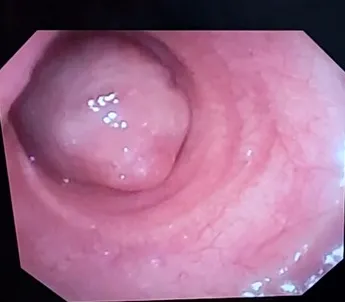

В в/3 трахеи, слева имеется образование с экзофитным ростом, овальной формы 3.5х2.5 см,занимающее почти весь просвет трахеи, розового цвета, при пальпации плотной консистенции, на толстой ножке.